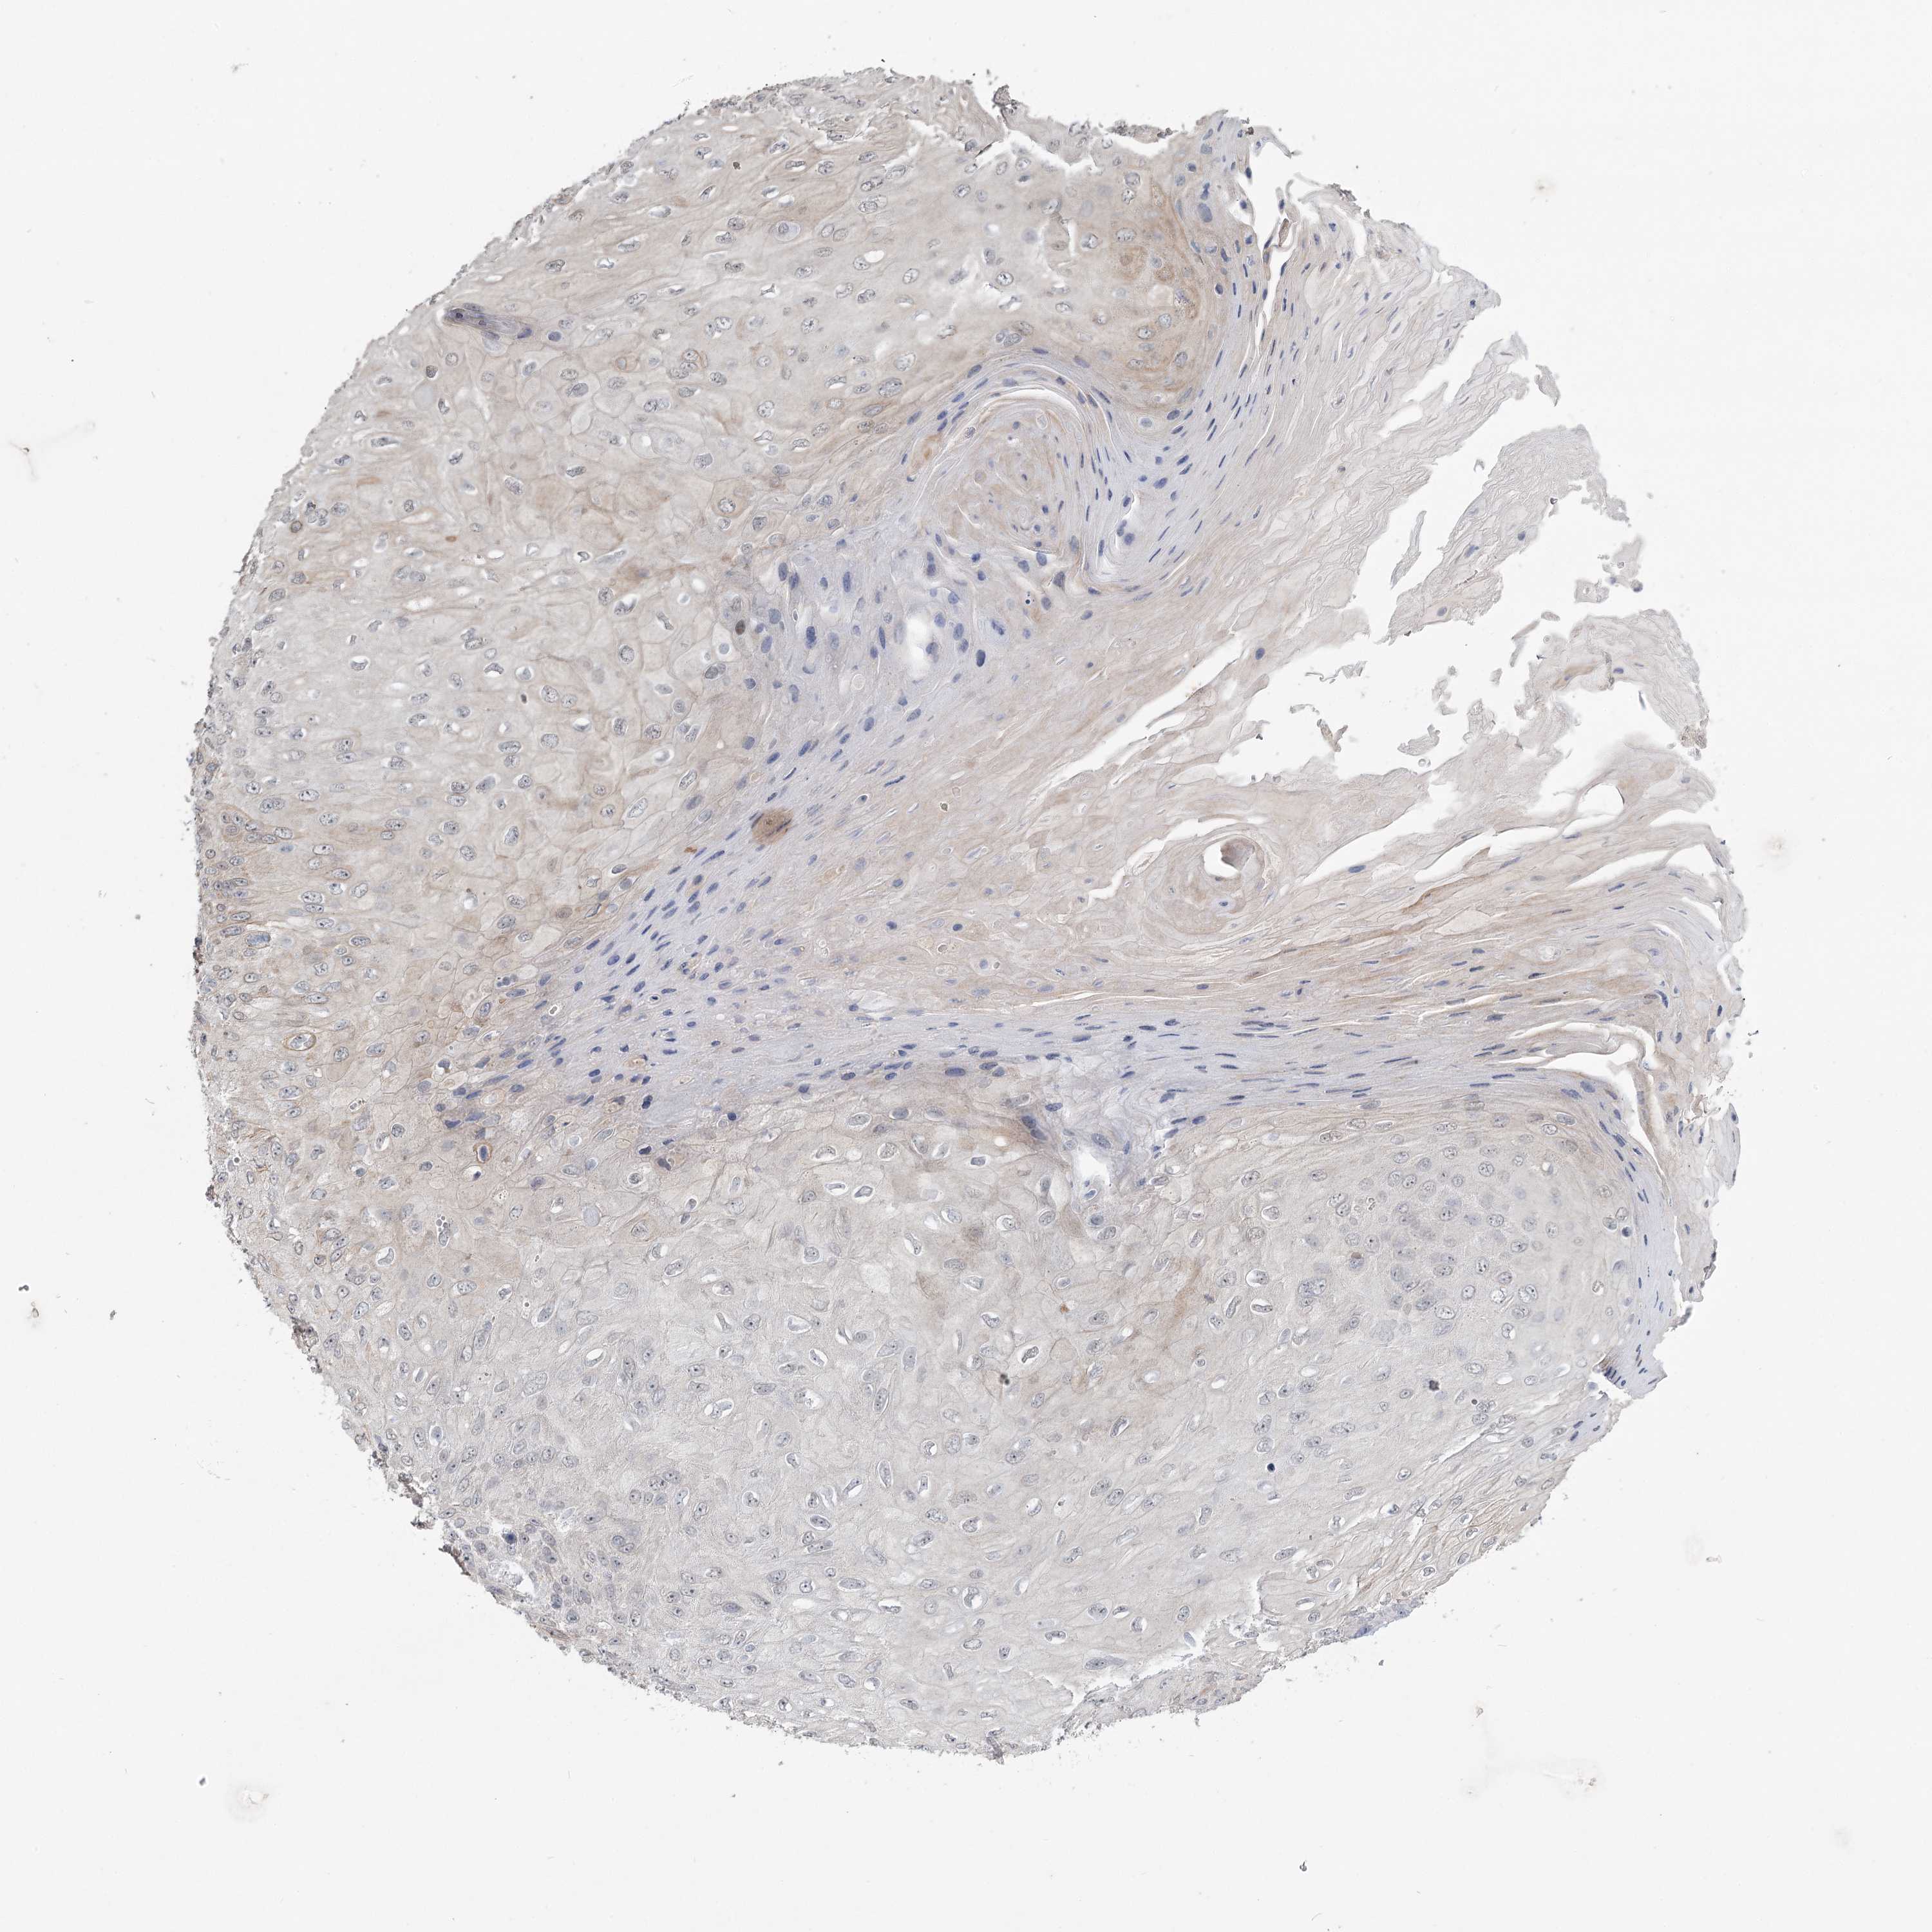

Basal cell and squamous cell cancer

SKIN CANCER - Protein expressioni

A mouse-over function shows sample information and annotation data. Click on an image to view it in a full screen mode. Samples can be filtered based on level of antibody staining by selecting one or several of the following categories: high, medium, low and not detected. The assay and annotation is described here.

Each image is clickable and will lead to virtual microscopy that enables deeper exploration of all samples and also displays staining intensity scores, fraction scores and subcellular localization as well as patient and tissue information for each sample.

Antibody CAB034226

Squamous cell carcinoma, NOS